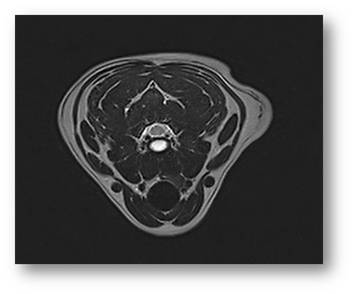

The next generation Magnus AIP Vet-MRI veterinary MRI system was designed exclusively for animals.  The system utilizes our novel magnet design providing superior field homogeneity, large 16" field of view and excellent patient access. Our user friendly veterinary specific software includes optimized protocols for each anatomical site and allows maximum flexibility in customizing clinical protocols and post imaging processing.  The wide range 2D and 3D sequences and imaging techniques, including over-sampling, fast imaging, fat and water suppression, diffusion-weighted imaging and high resolution imaging guarantee superior image quality.  The Magnus AIP Vet-MRI is 100% digital, network ready and DICOM 3.0 compatible for remote reading and easy image archiving.

Large 16" Field of View

Superior Imaging Quality

• Veterinary Specific Phased Array Multi-Channel Coils